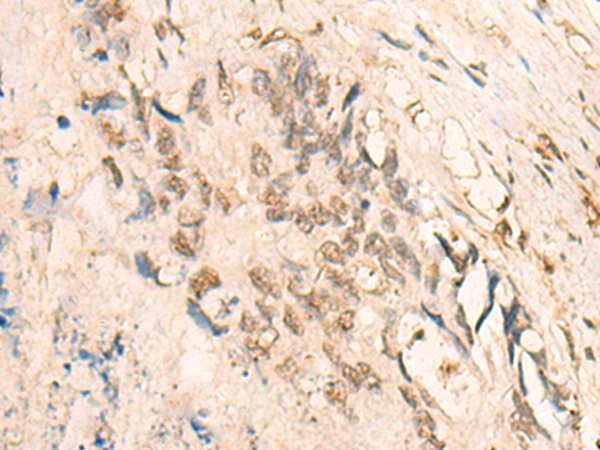

IHC positive control: |

Human lung cancer and Human colorectal cancer |

IHC Recommend dilution: |

25-100 |